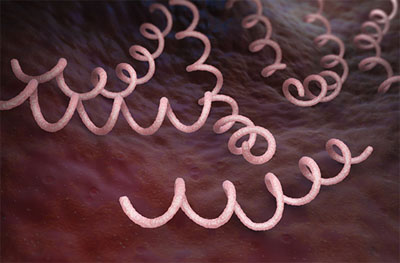

Karakteristik treponema pallidum, morfologi, habitat / Biologi | Thpanorama - Jadikan diri Anda lebih baik hari ini!

Karakteristik treponema pallidum, morfologi, habitat / Biologi | Thpanorama - Jadikan diri Anda lebih baik hari ini!